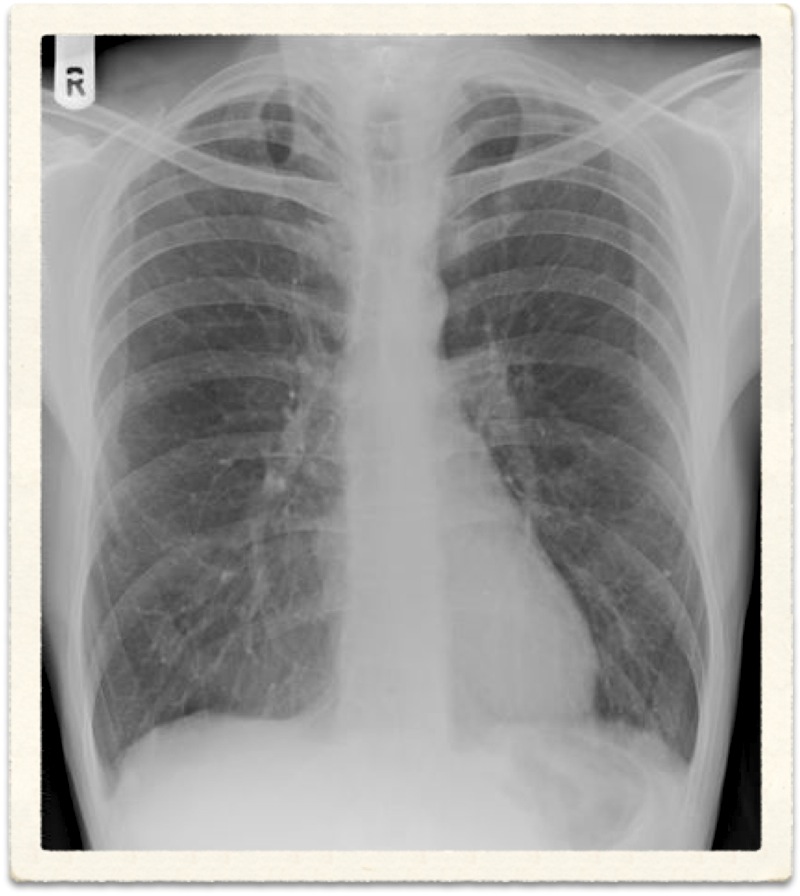

Radiological Report: Cardiac size within normal limits. Both lungs show severe overinflation typical of COPD. No sign of mass or consolidation.

Chronic bronchitis cannot be diagnosed radiologically. Although findings such as increased lung markings or tubular opacities, bronchial wall cuffing (thickening) can be seen with bronchitis, they are nonspecific. The main reason for getting a chest X-ray is to exclude other conditions, such as bronchiectasis, which can mimic the disease clinically.